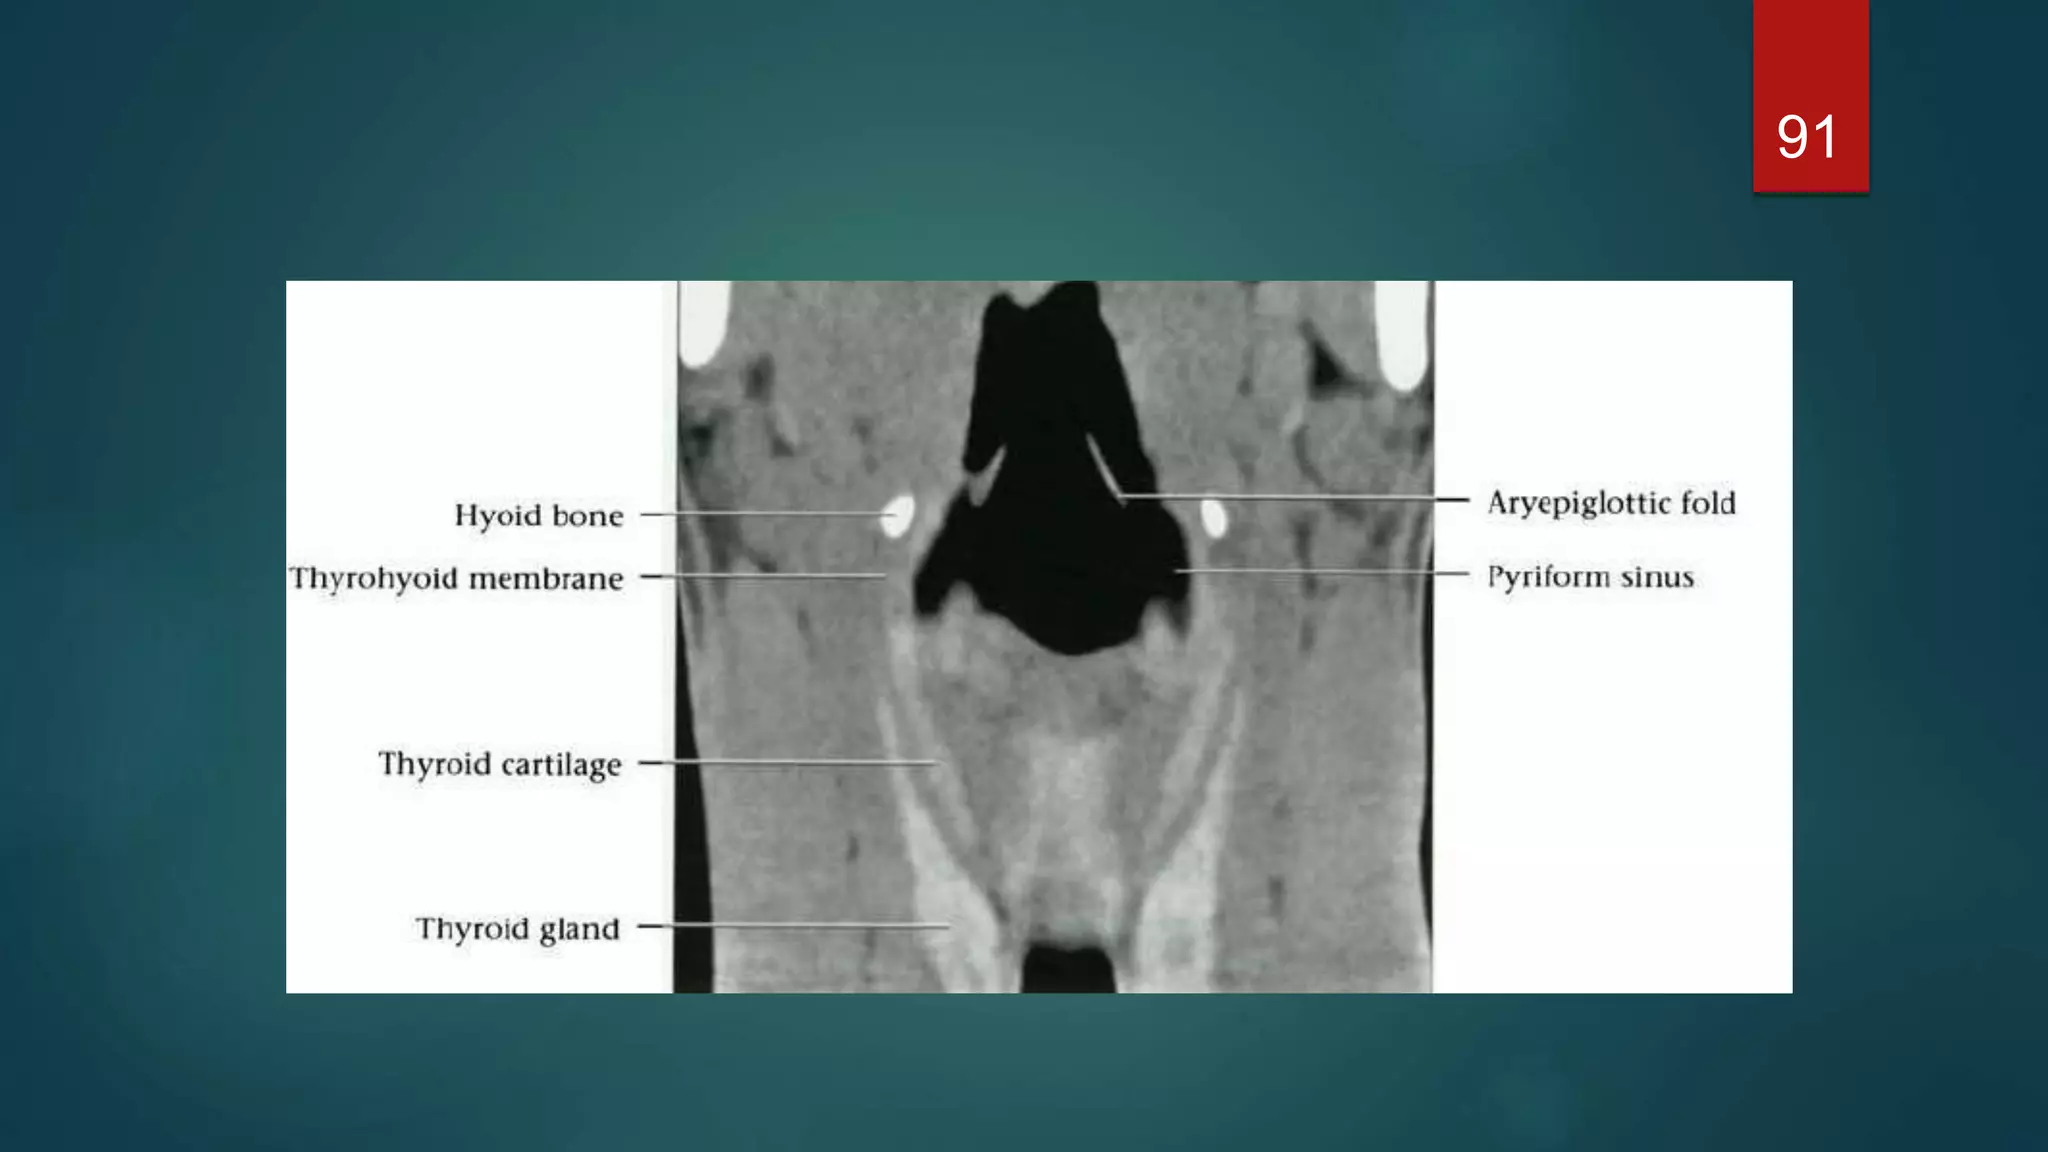

Cross-sectional anatomy of the

larynx

Supraglottic level

 The larynx is anterior to the piriform

sinuses, separated from them by the

aryepiglottic folds.

Cross-sectional anatomy ofthe larynx Supraglottic level  The larynx is anterior to the piriform sinuses, separated from them by the aryepiglottic folds. 71